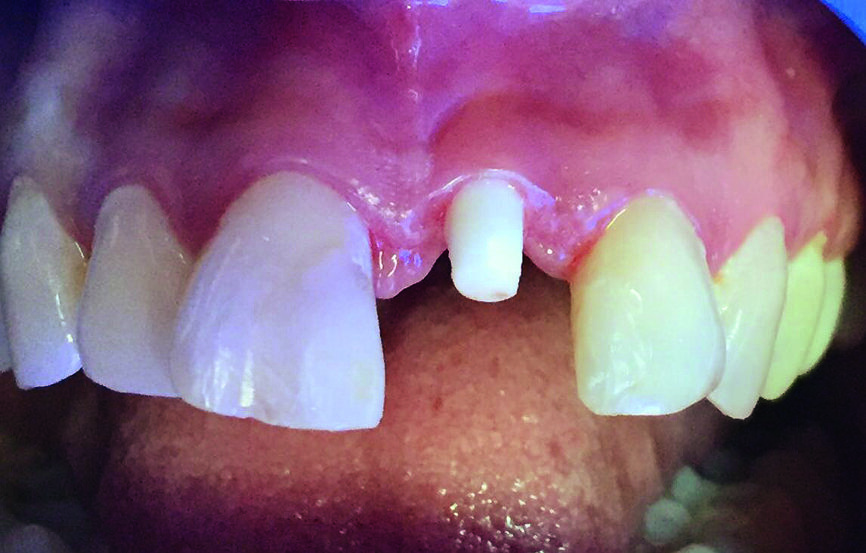

Fig. 4 : Stade de la cicatrisation après quatre mois

Des empreintes ont été prises quatre mois plus tard et l’implant qui remplaçait la dent 21 a été restauré avec une couronne en zircone (Fig. 4). Les contacts occlusaux de la couronne ont été vérifiés à l’aide de papier à articuler d’une épaisseur de 12 microns (Fig. 5).